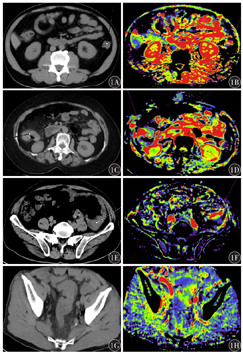

不同临床病理分期患者的AEF定量彩图表现见图1。

Ⅰ、Ⅱ、Ⅲ、Ⅳ期结直肠癌患者AEF值分别为(72±9)%、(65±11)%、(60±12)%、(52±10)%,差异有统计学意义(F=22.15,P<0.001),Ⅳ期AEF值低于Ⅰ+Ⅱ期(t=7.56,P<0.001);对照组与结直肠癌组AEF值分别为(85±6)%与(62±12)%,两组差异有统计学意义(t=18.66,P<0.001);结直肠癌临床病理分期与AEF值呈负相关(r=-0.548,P<0.05)。

在结直肠癌发生、发展过程中,病变部位的血管生成增加,复杂的血管网是肿瘤生长和转移的基础[8]。AEF定量彩图及AEF值可以从微循环水平反映病变内部血管血供特征,同时可避免受检者接受额外的辐射暴露。Kim等[9]首先提出肝脏AEF值可以提高对常规多期增强CT扫描血流动力学变化不太明显的小肝癌的诊断效能。容鹏飞等[10]使用肝AEF及肝与脾AEF比值来评估肝硬化患者肝功能损害程度。冯智超等[11]研究发现AEF定量彩图对肝脏局灶性结节增生与肝细胞癌有一定的鉴别诊断价值。Mao等[12]研究表明应用肝AEF特征可以预测经动脉化疗栓塞治疗的肝细胞癌的治疗反应。可见目前AEF定量彩图多用于肝脏病变的研究,但在结直肠肿瘤中的研究报道较少。本研究结果表明,结直肠癌临床病理分期与AEF值呈负相关,可见随着临床病理分期的升高,结直肠癌的动脉血供逐渐减少,而静脉血供相对增多;原因可能为:(1)晚期结直肠癌患者肿瘤体积增大,其所处内部空间有限,肿瘤组织内血管受压,压迫动脉导致部分动脉血管不完全充盈而显示动脉血供减少,压迫静脉则导致静脉回流障碍而充盈量较大;(2)肿瘤发展过程中新生血管逐渐增多,血管壁还不够成熟,其内较多静脉血通过,因此可以预测晚期肿瘤患者的AEF值比早期减小。这与王丹丹等[13]使用CT能谱成像技术研究结直肠腺癌,显示肿瘤的静脉期摄取率高于动脉期的结果一致。基于这些生理病理改变和研究结果,AEF值对于结直肠癌的诊断效能较高,且灵敏度与特异度可以随着临床病理分期升高而增高,因此AEF值可用于结直肠癌的诊断与临床病理分期。